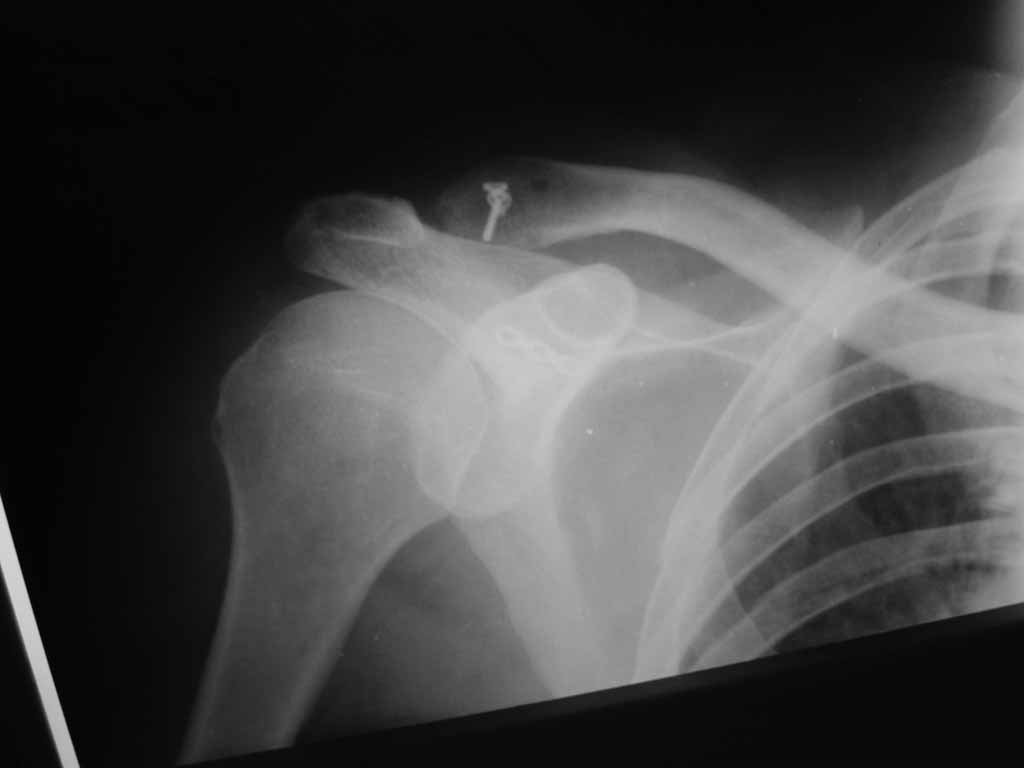

Re: Лечение вывиха акромиального конца ключицы

В Пензенской ОКБ им. Н.Н.Бурденко мы в свежих случаях (до 3 недель) проводим либо фиксацию по Веберу (2 спицы и стягивающая проволочная петля), либо фиксацию крючковидной пластиной (если больной согласен ее приобрести).

В застарелых случаях необходимо кроме фиксации сустава дополнительно проводить пластику ключично-клювовидной связки любым доступным способом.

В свежих случаях (до 3 недель) глубоко индифферентно, чем фиксировать, главное - низвести в сустав. Делаем по Ли (субакромиально изогнутым стержнем, потом в косынку, стержень удаляется под местняком через 6 недель), либо крючковидной пластиной.

В застарелых - процедура Мамфорд (удаляем 1,5 см акромиального конца ключицы) с одномоментной пластикой ключично-0клювовидной связки + для успокоения души пару спиц при низведенной до уровня сустава ключицы.

Если начать сначала, то предпочтение отдаем класификации Роквуда. Использовал разные методики оперативного лечения. Откыртое вправление и фиксация спицами акромиально-ключичного сустава с пластикой ключично-клювовидной связки лавсаном, а также баз пластики звязки. Результаты одинаковые. Мое мнение, что в свежем случае можна обойтись и без вмешательства по пластике ключично-клювовидной связки если мы открыто вправляем вывих и фиксируем его например спицами - главное сблизить вправленнием волокна связки. Использовал методику по Веберу и крючковидную пластинку. По Веберу нравится, особенно если нужна хорошая фиксация. Проблем с миграцией, переломом и прочими проблемами при ипользовании спиц не было ни разу. Пластинка - красиво, быстро, для активных пациентов или спортсменов подходящий метод лечения, хотя и дороже. Застарелый случай был только один. Тогда оперировали с открытым вправлением, фиксацией спицами и пластикой ключично-клювовидной связки - результат хорошый.

На недавнем конгрессе Европейского общества хирургии плеча и локтя (SECEC) довелось слышать хороший доклад из Китая по крючковидным пластинам. Из доклада и после общения с авторами для себя сделал следующие выводы:

1. У 1/3 пациентов проблемы с акромионом отсутсвуют, у 1/3 - обратимый лизис/повреждение, и у 1/3 - необратимый лизис/повреждение.

2. Категорически не рекомендуется применение крючковидной пластины у скелетно-незрелых пациентов.

3. С установленой крючковидной пластиной запрещается отведение больше 90 градусов (т.к. происходит ротация крючка и "разминание" акромиона) и занятия спортом (баскетбол, волейбол).

4. Эти пластины необходимо обязательно удалять (говорят через три месяца).

В нашей клинике мы обычно применяем фиксацию по Веберу или hook пластину (последнее сейчас реже). У пожилых мультиморбидных пациентов можно и не фиксировать, это же только косметический дефект.